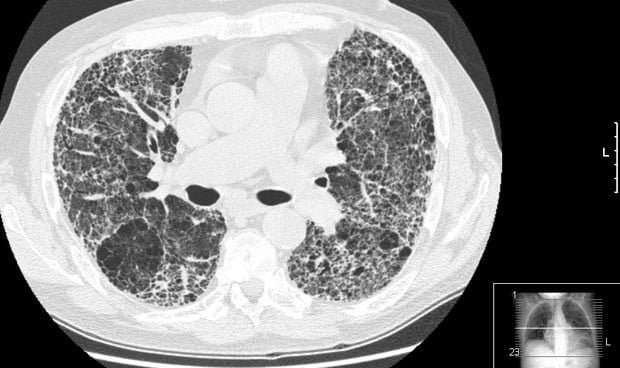

La Sociedad Española de Neumología y Cirugía Torácica (Separ) ha advertido de que la pandemia de Covid-19 ha condicionado un "retraso diagnóstico" en el último año en fibrosis pulmonar idiopática (FPI) y de linfangioleiomiomatosis (LAM), lo que conlleva peor pronóstico, tras "años trabajando para mejorar el diagnóstico rápido".

La FPI afecta a 10 personas por cada 100.000 habitantes, más a hombres que a mujeres, especialmente mayores de 60 años. Se produce por una reparación anómala del pulmón que provoca una cicatriz (fibrosis). Se llama "idiopática" porque "hasta ahora no se ha podido identificar el agente causal inductor del daño pulmonar inicial". "Aun así, en los últimos años hemos mejorado en el conocimiento de la patogenia de esta enfermedad y han aparecido tratamientos antifibróticos que antes no existían y que nos han permitido mejorar la expectativa de vida de estos pacientes", explica María Molina, neumóloga y directora del PII-EPID (acrónimo de Programa Integral de Investigación de las EPID), de Separ.

Actualmente, "la pandemia de Covid-19 ha tenido un efecto negativo en el manejo de estos pacientes". "Nos están llegando casos en fases muy avanzadas, con un deterioro que no veíamos desde hace una década, debido al colapso asistencial de Atención Primaria y Neumología hospitalaria. Hay que volver a poner en marcha estos circuitos de diagnóstico rápido cuanto antes para enfermedades graves como la FPI o la LAM, entre otras", remarca Molina.

"El problema es que no se ha invertido lo suficiente en recursos humanos en la atención primaria, con la pandemia de Covid-19 se ha evidenciado y nos encontramos con casos de FPI desatendidos, porque los recursos humanos se dedican al Covid-19. Cuando la fibrosis pulmonar se diagnostica en una fase correcta, podemos ofrecer el tratamiento óptimo que modifica el curso natural de la enfermedad. Cuando se diagnostica en una fase avanzada la supervivencia media es menor de 5 años. Todo depende de en qué fase llegue el paciente al especialista, es decir, si llega a tiempo de recibir los tratamientos modificadores de la enfermedad o no y con o sin opción de trasplante", explica la doctora.